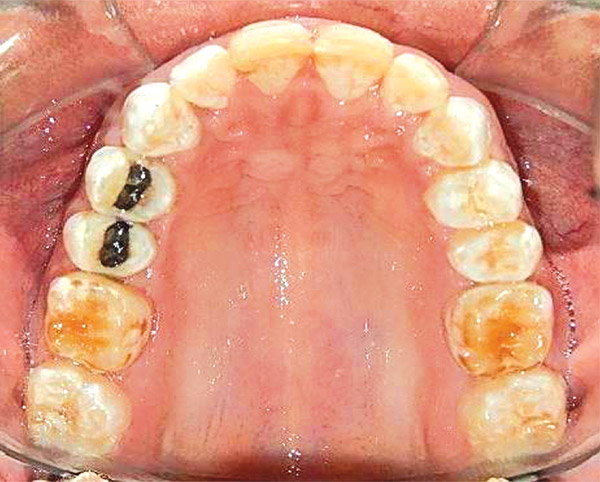

En las fotografías intraorales se muestra la fluorosis dental Tf4 y Tf7, las relaciones molares clase II molar y canina bilateral (Figura 3 y 4), el apiñamiento severo superior e inferior, con el órgano dental 35 en infraoclusión. El overbite aumentado y las líneas medias dentales no son coincidentes (Figura 5), las formas de arco superior e inferior son cuadradas (Figura 6 y 7).

Figura 6. Oclusal superior.

Figura 7. Inferior.